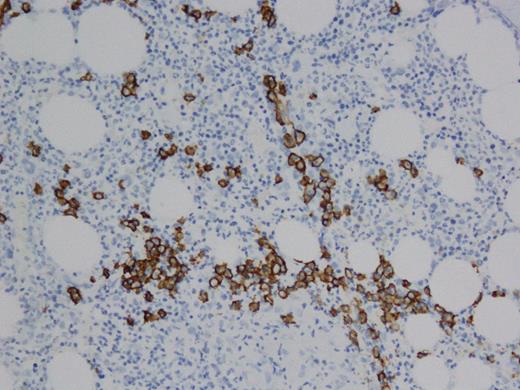

A 60 year old female with past medical history of stage IIA Hodgkin's lymphoma diagnosed in 1992, treated with total nodal radiation with recurrence in 1997 treated with 6 cycles of ABVD achieving complete remission. The patient was found to have hypercalcemia (11.0 mg/dL) and renal failure (1.29 mg/dL) in March 2011. Hypercalcemia workup revealed suppressed PTH (<3 pg/ml), elevated ionized calcium (6.1 mg/dL) elevated parathyroid related peptide (38pg/ml), normal vitamin D and ACE levels. Serum protein electrophoresis (SPEP) showed M-spike of 0.9 g/dL. Immunofixation electrophoresis (IFE) demonstrated an IgG monoclonal immunoglobulin without a corresponding light chain (figure 1). Free serum kappa and lamda light chains were within normal limits. Serum IgG was elevated (4678 mg/dL), normal IgA (127 mg/dL) and low IgM (39mg/dL). Also, Beta-2 microglobulin was elevated (14.3 mg/L). The patient was seen by hematology for monoclonal gammopathy and hypercalcemia and a solid tumor work up was recommended given that the most common the mechanism of hypercalcemia for multiple myeloma is osteoclast-driven and not PTHrP related. CT chest/abdomen/pelvis, bone scan, bone survey, mammography, pelvis ultrasound were negative. Bone marrow biopsy was performed November 2011 showing 10% plasma cells (PC) by CD138, non clonal by kappa/lambda. Patient was placed on zolendonic acid for hypercalcemia and her renal function and hypercalcemia continued to worsen over a period of months. A kidney biopsy was performed in April, 2012 and revealed acute and chronic tubulointerstitial nephritis with secondary glomerulosclerosis and mild interstitial fibrosis and tubular atrophy suggestive of sarcoidosis and the patient was placed on a course of prednisone with transient improvement in calcium and renal function. The patient presented in emergency room in April 2013 with altered mental status. She was found to have hypercalcemia (12.0 mg/dL), renal failure (1.55 mg/dL),). SPEP revealed M-spike 0.64 g/dl. IFE displayed a broad band of IgG heavy chain, without associated light chains and severe depression of the non-monoclonal IgG. Serum immunoglobulins demonstrated elevated IgG (2110 mg/dL), normal IgA (46 mg/dL) and decreased IgM (<21 mg/dL). Bone marrow biopsy showed 5% PCs (figure 2), non clonal by kappa/lambda- but exclusive for IgG by IHC, without any staining for IgA or IgM (figure 3). Cytogenetics were normal. Based on the constellation of findings and similarity to prior workup the patient was diagnosed with IgG heavy chain disease and therapy with cytoxan, dexamethasone, bortezomib was initiated. Calcium levels improved and she has recovered clinically; she is currently completing her second cycle of therapy. We plan to follow PTHrP levels along with routine paraprotein assessments.